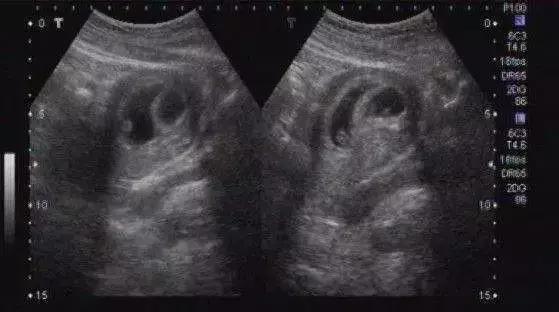

刚刚怀孕50天看孕囊是男是女准吗?

老百姓闲来无事,总喜欢找点事情娱乐一下。怀孕50天,超声看孕囊能看出男女才怪!

早孕期孕囊里包裹的除了胚芽还有一些羊水。我们可以想象一下,兜着水的气球,放在桌子上会变成什么形状。孕囊就是这种不规则的类椭圆体。

孕期,不管是腹壁B超还是经阴道B超,都是无法做到三维重建,只能根据超声检测到的2-3个径线来描述孕囊的大小。大家拿到手的B超报告,数值接近的,容易被理解为是圆形,有的数值差距太大,就被理解为椭圆形。

这个和男女半毛钱关系都没有,只是超声扫描到的切面不同测到的数值不同而已。比方说,一枚鸡蛋或者一颗扁扁的桔子。我们从不同的方位用灯光照射,看看投影都有神马形状:圆形、扁的、椭圆……正所谓横看成岭侧成峰,远近高低各不同。

B超能看到性别,得等到长出外生殖器

超声看到的是形态上的影像,当胎儿的外生殖器长到可以通过超声看到的程度,就可以进行检查了。一般需要怀孕3-4月以后了,不过误差也比较大。更何况,我们国家法律明令禁止孕期看性别,所以,你就别想拉。